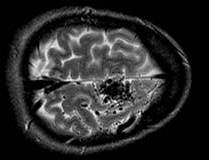

Click the following pictures for Questions

and Answers.

(The experience from past candidates inidcates that the

examiners expect you to be able to differentiate T1 from T2 weighted images.

The most commonly encountered scan in the examination is periventricular

plaques.)